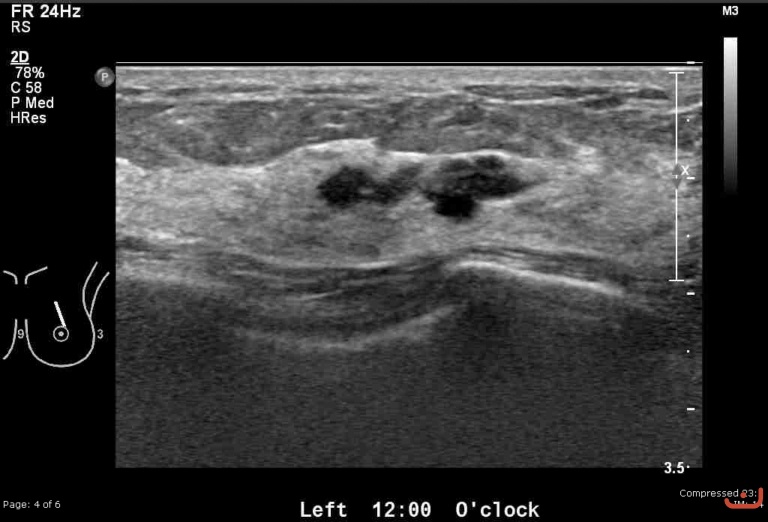

Malignant solid mass

Date

Thursday, 30 April 2015

180.53 KB (768 x 522 px)